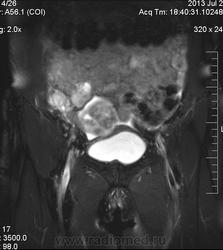

в-целом, cогласен. Карциноматоз тоже есть. Видится еще диффузный аденомиоз матки (задней стенки).

Мне кажется, что есть инфильтрация и передней стенки прямой кишки.